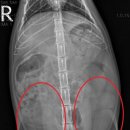

• 목련동물병원 | [목련동물병원] 고양이 자궁축농증 수술 케이스

경우 이러한 자궁축농증이나 유선종양 등의 질병을 예방하기 위해 중성화 수술을 해주시는 것을 권장드립니다. ​ 이상으로 고양이의 자궁축농증 수술 케이스 설명을 마칩니다. 감사합니다. ​ ​ ​ 목련동물병원 대구광역시 수성구 용학로 194 1층 ​ [ 목련동물병원 ] 주소 : 대구 수성구 용학로194 1층 문의 : 053-782-5475...

목련동물병원(2025-10-28 16:24:00)